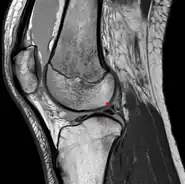

Posterior meniscofemoral ligament on MRI, sagittal